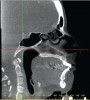

Figure 4a  Coronal section of 3D tomograph revealing axial alignment of posterior teeth. A) Dental alignment does not allow occlusal forces to be directed down long axis of teeth. Maxillary teeth had been tipped to the buccal to compensate for the transverse discrepancy. B) Teeth are positioned to allow occlusal forces to be directed down long axis of teeth.

Figure 4a

Figure 4b  Coronal section of 3D tomograph revealing axial alignment of posterior teeth. A) Dental alignment does not allow occlusal forces to be directed down long axis of teeth. Maxillary teeth had been tipped to the buccal to compensate for the transverse discrepancy. B) Teeth are positioned to allow occlusal forces to be directed down long axis of teeth.

Figure 4b